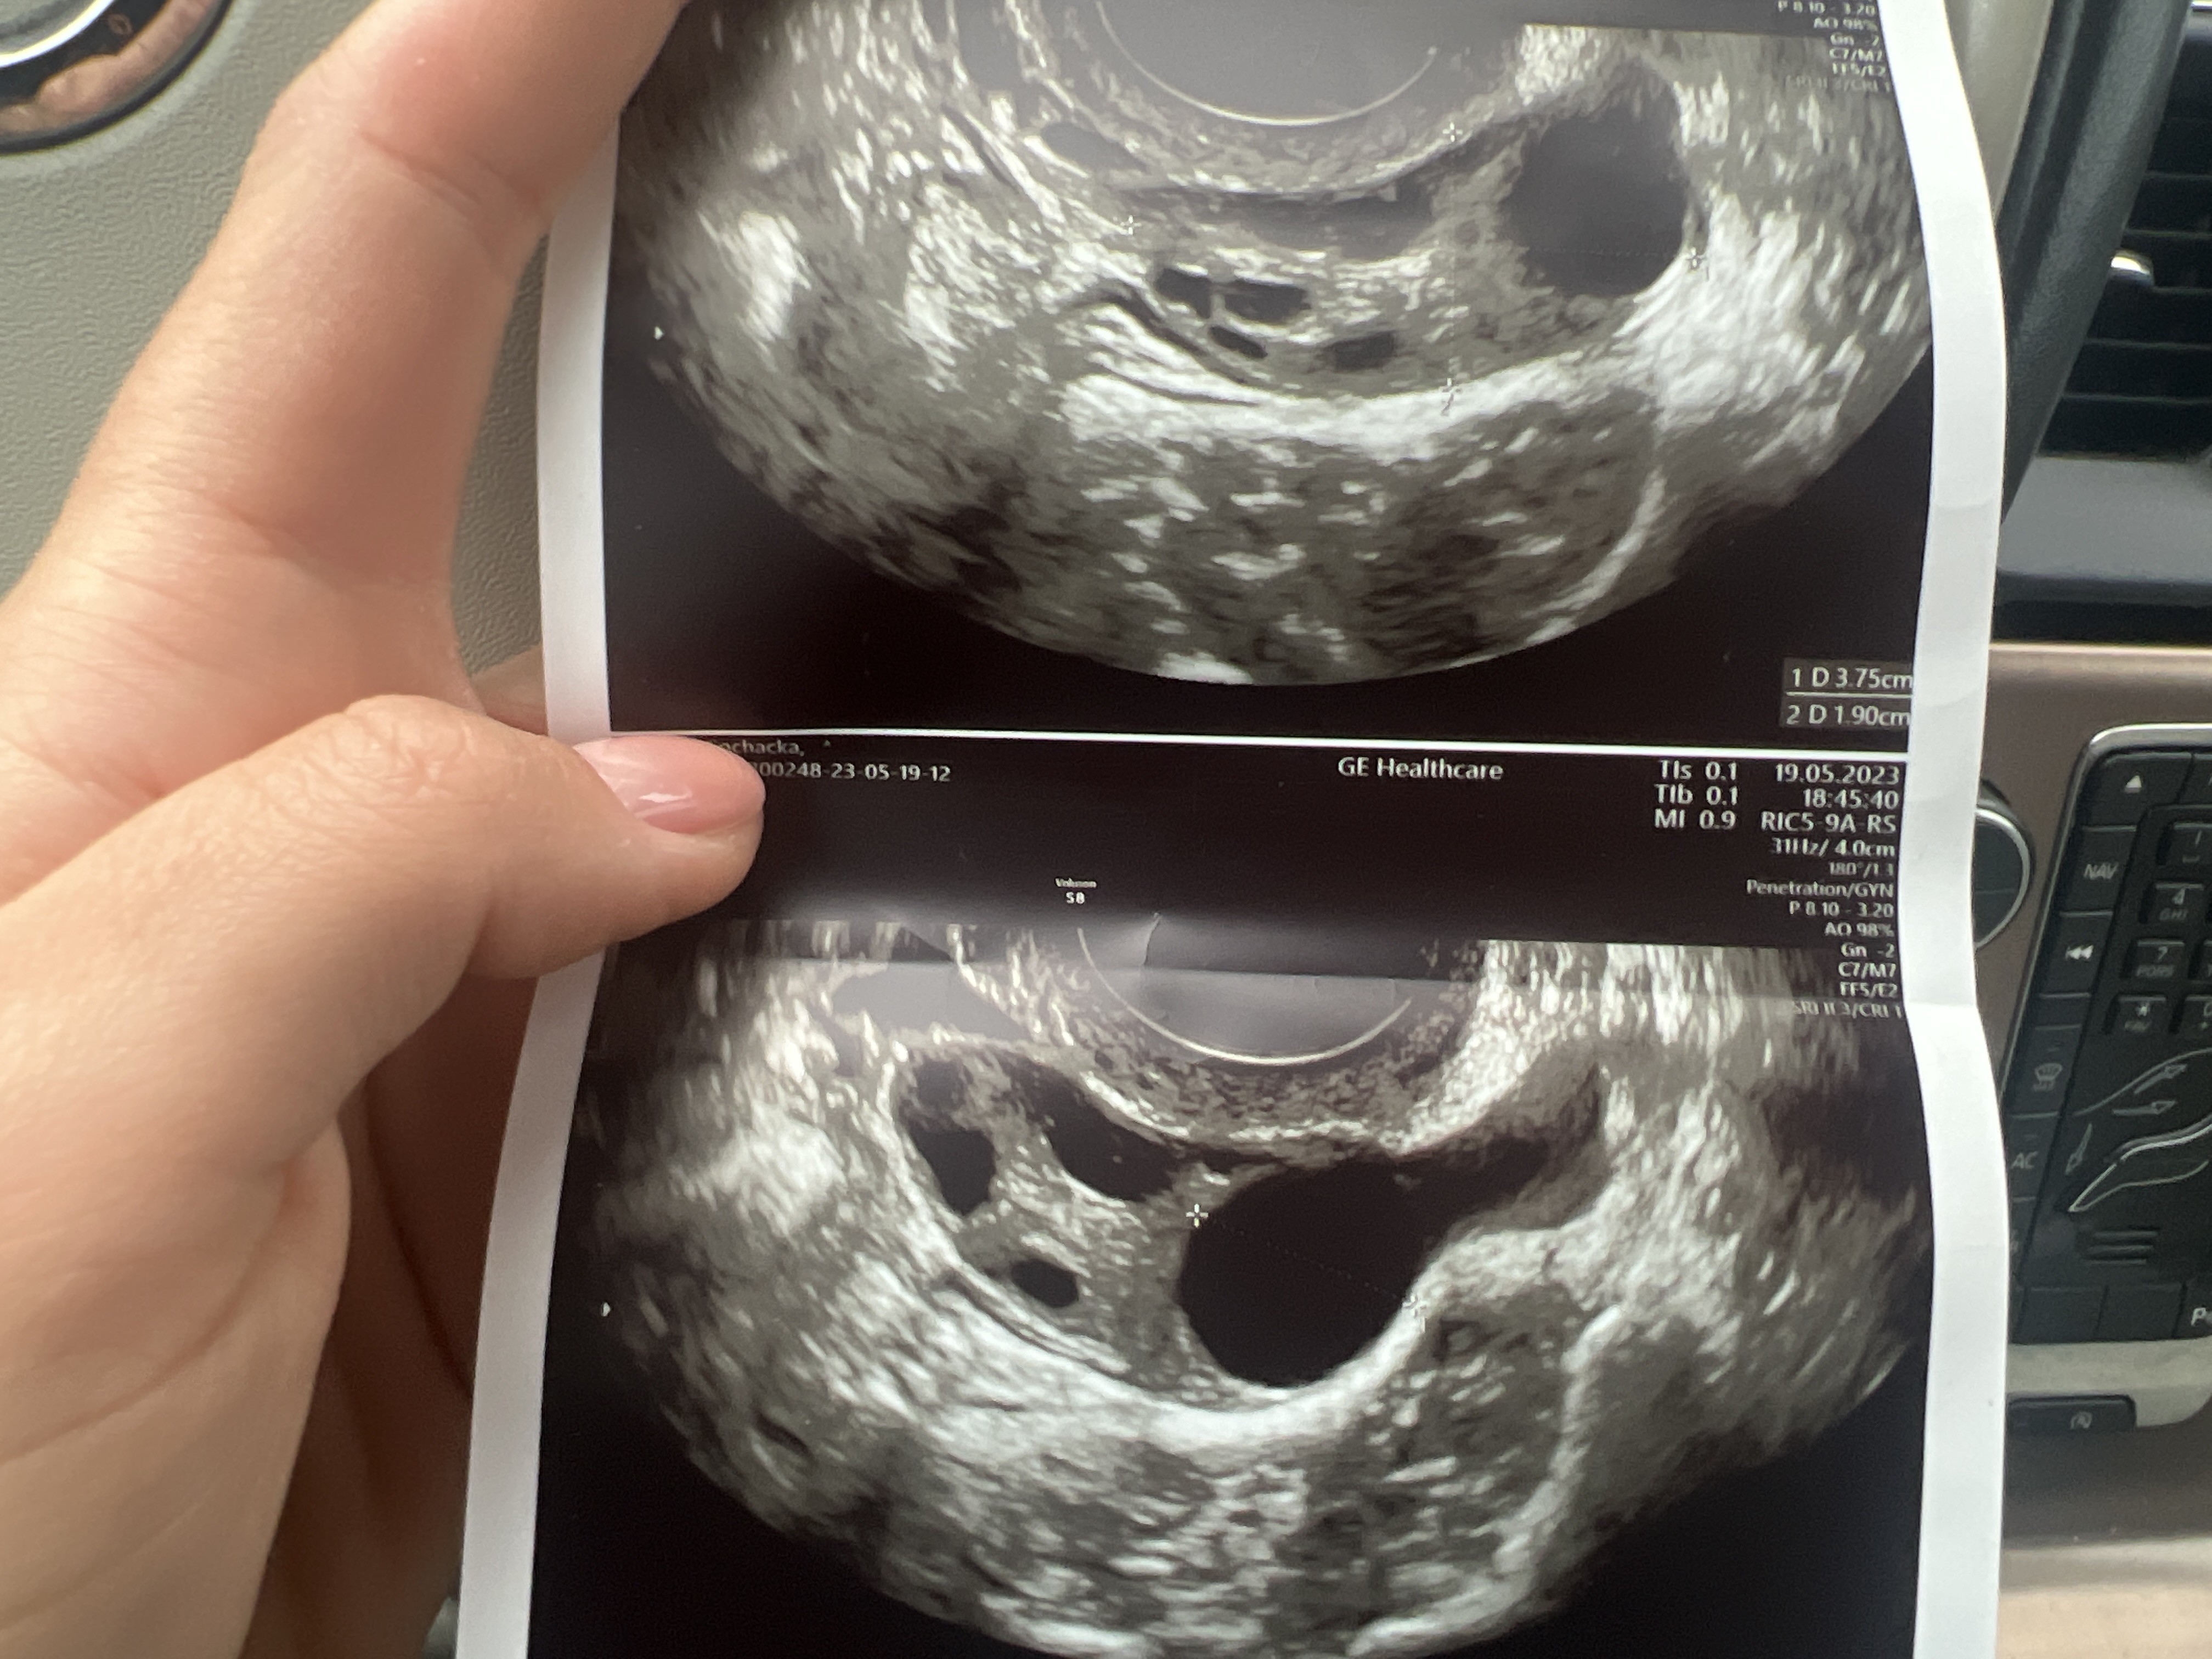

Hej dziewczyny! Od pol roku bezskutecznie staramy sie o dzidzie. Prawdopodobnie mam PCOS. Od poniedzialku pecherzyk nie urosl ani mm. Lekarka przyjela mnie po godzinach i nie mialam czasu z nia porozmawiac wiec mam do Was kilka pytan…

Załączniki

• image.jpg

image.jpg

1,4 MB · Wyświetleń: 268